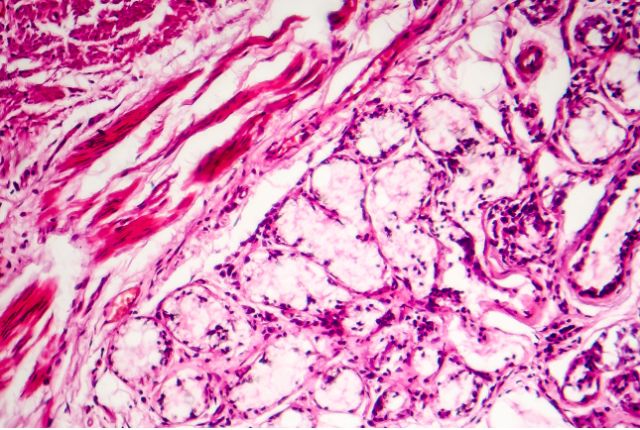

Le terme bronchite désigne une inflammation des bronches et des bronchioles, autrement dit une irritation des voies chargées d’acheminer l’air jusqu’aux poumons. Cette infection respiratoire est la manifestation d’une contamination par un virus hivernal, qui peut affecter les enfants comme les adultes. Elle se traduit essentiellement par une toux gênante. Cette affection est très fréquente, et touche environ dix millions de personnes chaque année dans l’Hexagone.

On désigne par bronchite aiguë une infection d’origine virale dans 90 % des cas, qui affecte la trachée et les voies respiratoires (bronches, bronchioles). Dans les 10 % de cas restants, c’est une bactérie qui en est la cause. Cette pathologie est généralement sans gravité et guérit sous une dizaine de jours, voire sous deux à trois semaines au maximum. Elle génère une toux sèche dans un premier temps, puis des expectorations dans un cas sur deux.

La bronchite chronique se réfère à une bronchite qui s’étend sur 3 mois consécutifs au minimum, et qui se répète ainsi depuis deux ans ou plus. Elle est souvent la conséquence de l’inhalation de substances toxiques (tabac, produits chimiques). Sans prise en charge médicale, elle peut évoluer vers une broncho-pneumopathie chronique obstructive (BPCO), puis vers une insuffisance respiratoire chronique potentiellement fatale au patient. C’est traditionnellement le type de bronchite observé chez les fumeurs.